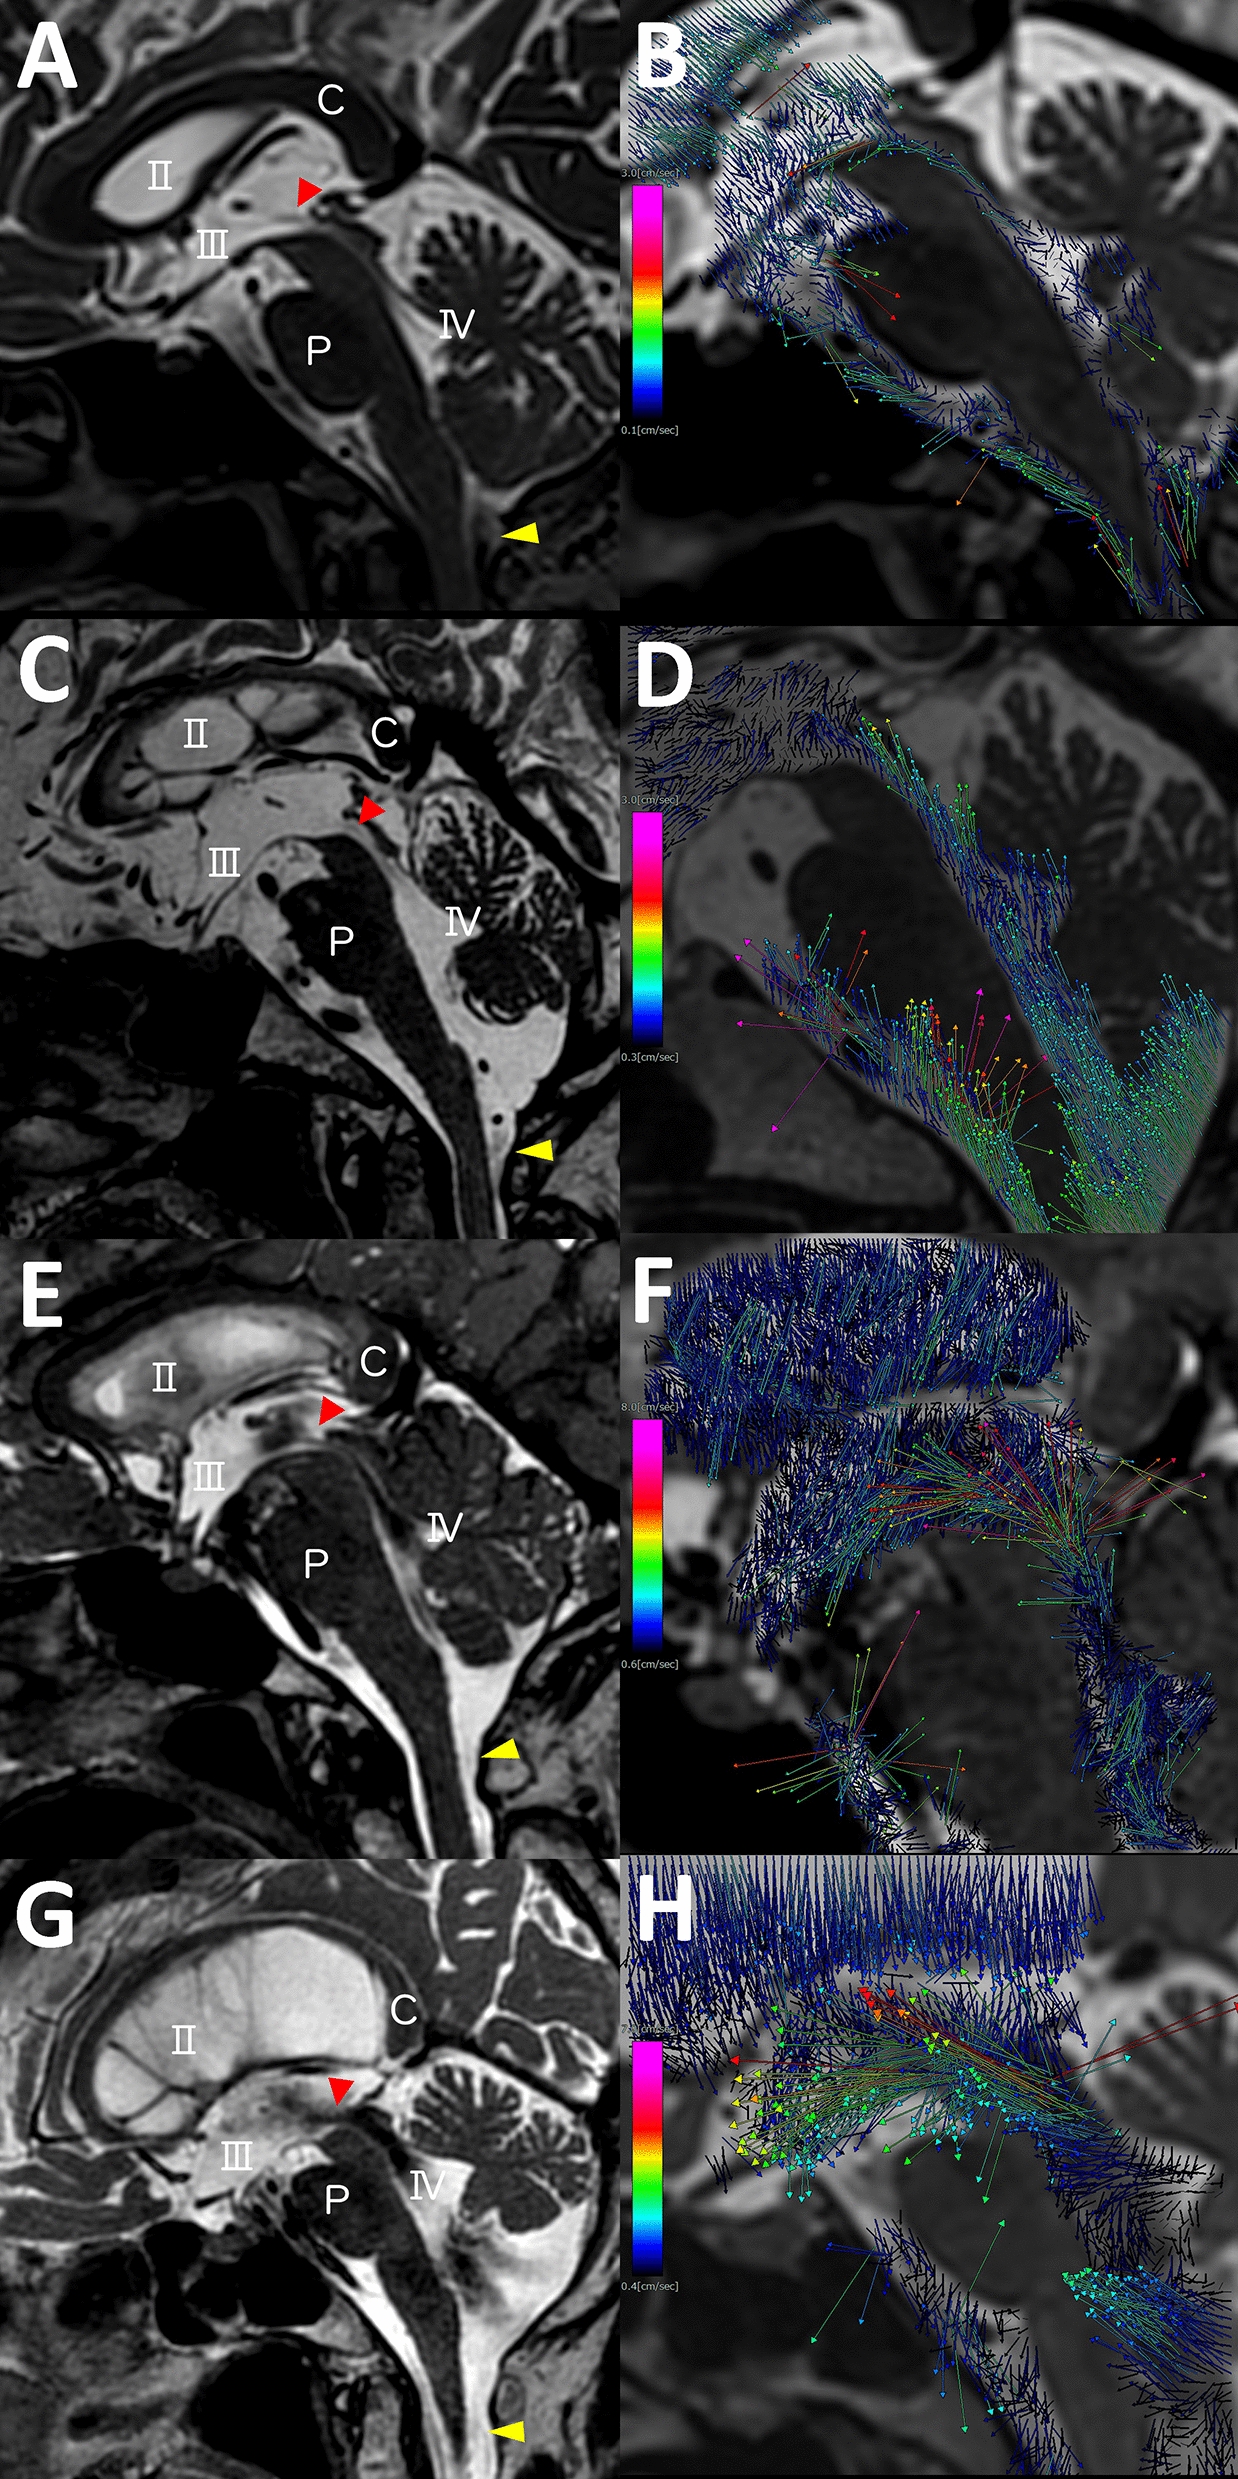

Fig. 1.

Flow void signs and flow vectors in normal elderly and three types of normal-pressure hydrocephalus (NPH). The left figures (a, c, e, g) depict the flow void sign at the top of the cerebral aqueduct (red arrow head) and dorsal region of the foramen magnum (yellow arrow head) from the T2-weighted fast spin-echo sequence, and the right figures (b, d, f, h) show the flow vectors from 4D flow MRI in normal elderly (a and b) and patients diagnosed with idiopathic NPH (c and d), secondary NPH (e and f) and late-onset congenital or developmental hydrocephalus (g and h). The colour of the vector represents flow velocity; pink indicates highest velocity and blue indicates lowest velocity. C: corpus callosum, P: pons, II: lateral ventricle, III: third ventricle, IV: fourth ventricle